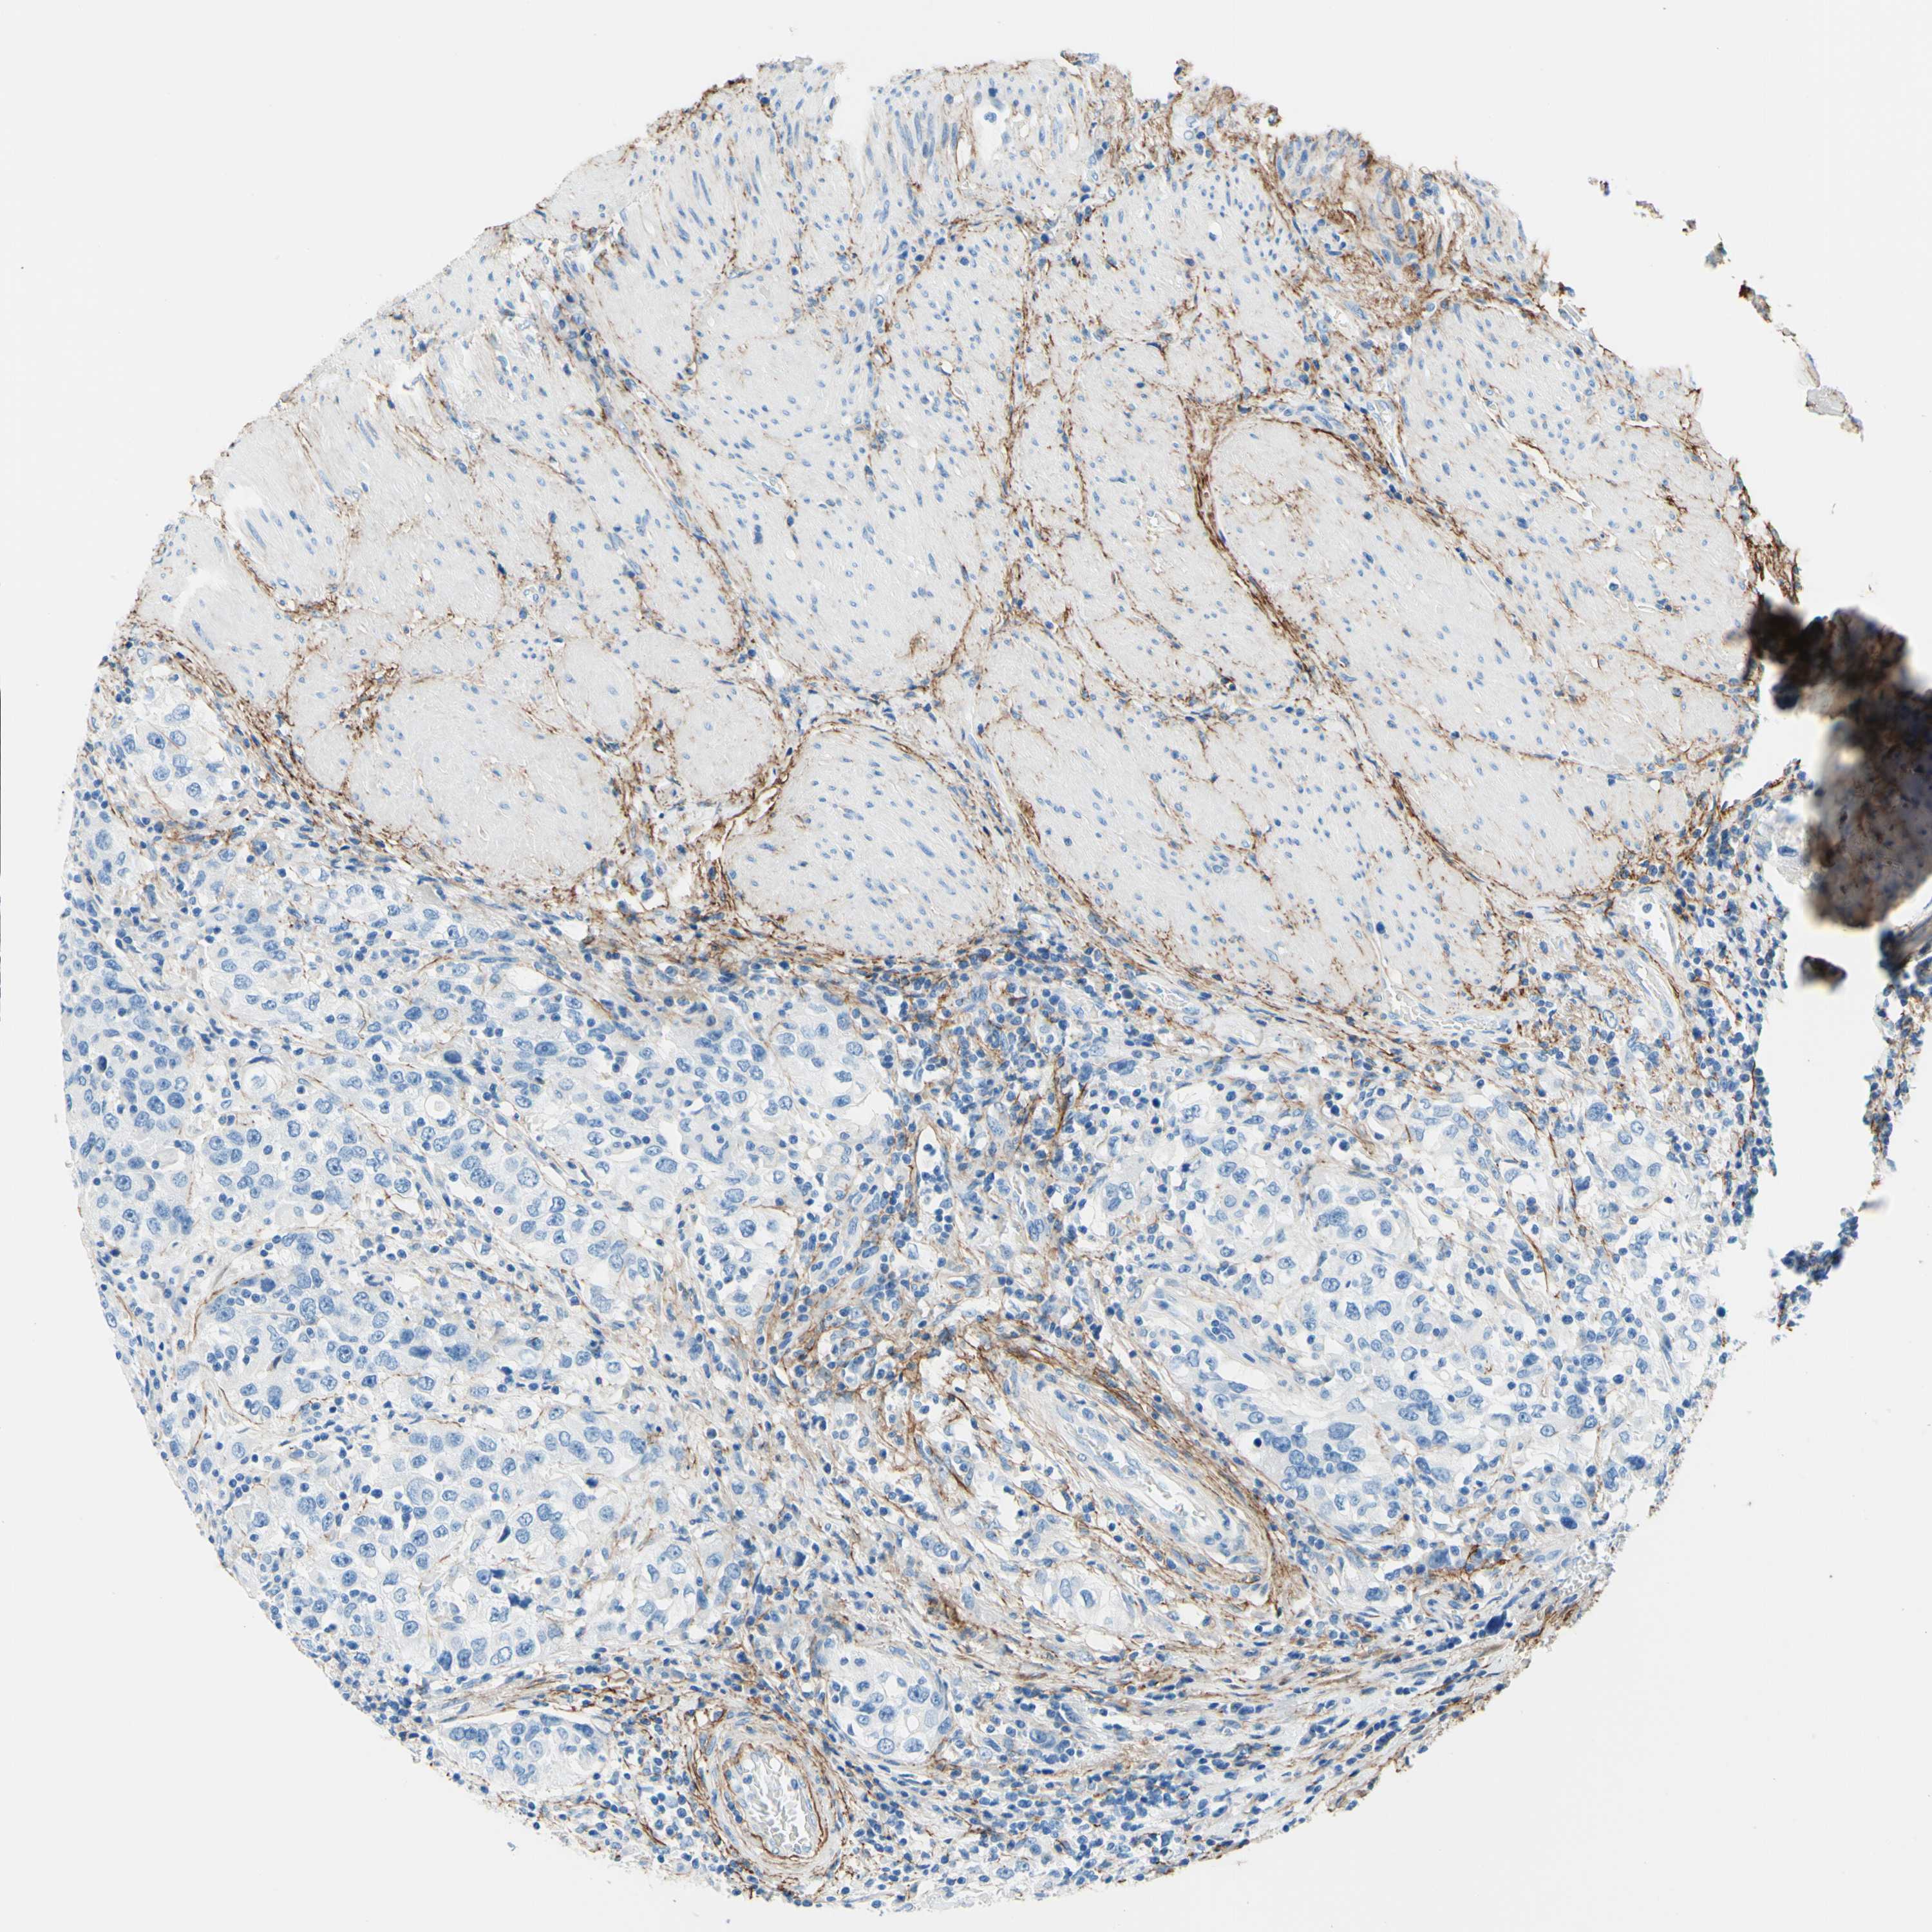

UROTHELIAL CANCER - Protein expressioni

A mouse-over function shows sample information and annotation data. Click on an image to view it in a full screen mode. Samples can be filtered based on level of antibody staining by selecting one or several of the following categories: high, medium, low and not detected. The assay and annotation is described here.

Note that samples used for immunohistochemistry by the Human Protein Atlas do not correspond to samples in the TCGA dataset.

Antibody stainingi

Antibody staining in the annotated cell types in the current human tissue is reported as not detected, low, medium, or high, based on conventional immunohistochemistry profiling in selected tissues. This score is based on the combination of the staining intensity and fraction of stained cells.

Each image is clickable and will lead to virtual microscopy that enables deeper exploration of all samples and also displays staining intensity scores, fraction scores and subcellular localization as well as patient and tissue information for each sample.

Antibody HPA010553

Staining

High

Medium

Low

Not detected

Intensity

Strong

Moderate

Weak

Negative

Quantity

>75%

75%-25%

<25%

None

Location

Nuclear

Cytoplasmic/membranous

Cytoplasmic/membranous,nuclear

Urothelial carcinoma, Low grade

Urothelial carcinoma, High grade